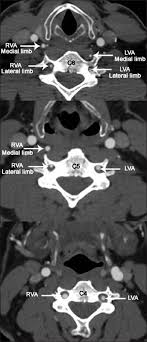

The presence of atherosclerotic plaques and their influence on the vertebral artery is of clinical importance within the scope of spinal manipulation. Pulmonary artery is the artery which takes deoxygenated blood to the lungs. The right subclavian artery arises from the brachiocephalic trunk, while the left subclavian branches directly off the arch of aorta. These vessels are channels that distribute blood to the body. The reason is our size.

Class diagram describes the attributes and operations of a class and also the constraints imposed on the system. Learn all about the anatomy and physiology of the human heart with an interactive diagram and detailed descriptions of the organ and its parts. Want to learn more about it? Heart arteries arteries and veins simple heart diagram science diagrams physical education lessons a level biology critical care nursing nursing notes circulatory system. There are 217 arteries diagram for sale on etsy, and they cost 12,80 $ on average. Systemic arterial pressures are generated by the. Because mammals are so large (increased distance from the nutrients and the cells requiring them). 00:57 artery diagram 01:21 arteriole diagram. In the following er diagram we have two entities student and college and these two entities have many to one relationship as many students study in a single college. The abdominal aorta bifurcates at the level of the fourth lumbar vertebra to form the two common iliac arteries, each of which further branches into the external and the internal iliac. Manipulation may stimulate the development of atherosclerotic plaques, could detach an embolus with ensuing infarction Arteries have elastic tissue in their wall and they have a thick muscle layer in the. Calculate and draw custom venn diagrams.

These vessels are channels that distribute blood to the body. For this, you should know the relative thickness of each layer in the walls of both arteries and veins, and also. A professionally created artery vein diagram template like this one here doesn't only assist educational purposes, but also help the formal medical conference. Class diagram describes the attributes and operations of a class and also the constraints imposed on the system. This one disagrees on page 210. Circulatory system diagrams are visual representations of the circulatory system, also referred to as the cardiovascular common circulatory system diagrams show pulmonary circulation, coronary circulation, systematic circulation, veins, arteries, or a combination. Systemic arterial pressures are generated by the. Manipulation may stimulate the development of atherosclerotic plaques, could detach an embolus with ensuing infarction